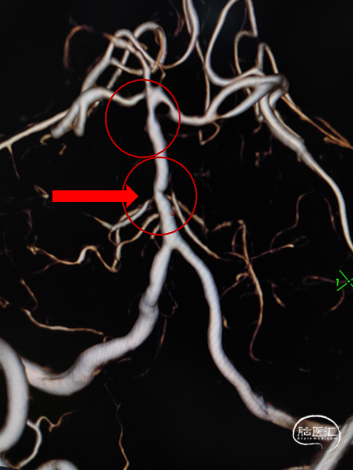

MRA:基底动脉重度狭窄

2、基底动脉中下段重度狭窄;

基底动脉狭窄位于双侧AICA开口处,且无双侧PICA,其供血区由双侧AICA、SCA分支代偿供血。

术中如何扩张基底动脉的同时保护双侧AICA通畅是手术成功的关键。